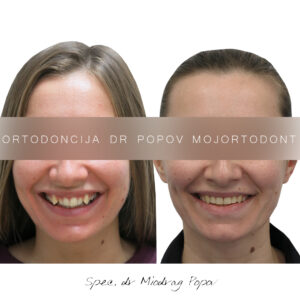

Dvogodišnja transformacija osmeha!

Nakon dve godine posvećene terapije, rezultati su više nego očigledni!

Osmeh je sada harmoničan, zagrižaj je funkcionalan, a svi zubi su na svom mestu.

Ovakvi slučajevi zahtevaju strpljenje, preciznost i poverenje između pacijenta i ortodonta – i ovo je još dokaz da se trud zaista isplati!